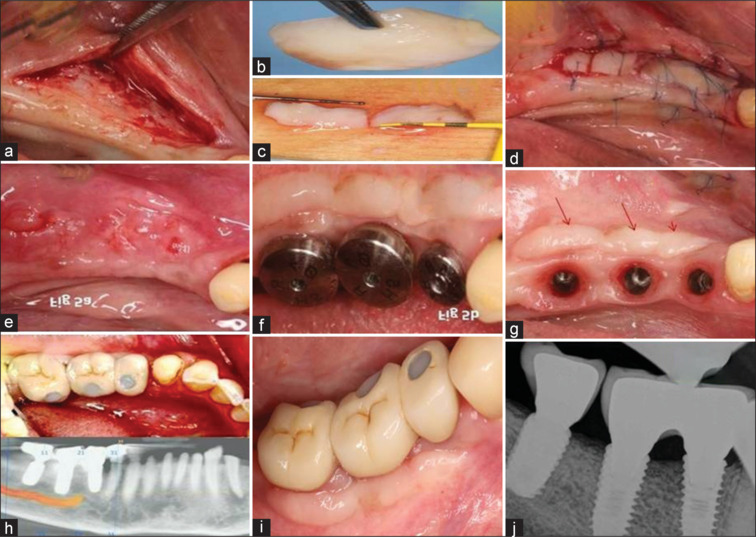

Successful multiple implant-supported prosthetic rehabilitation of Siebert class I alveolar defect at mandibular posterior site utilizing Khoury split bone block graft technique and free gingival grafting.

Insufficient dimension of alveolar bone and reduced width of keratinized gingiva may be the consequence of tooth loss accompanied by adaptive transformation. It creates a challenging situation for the clinician, especially in terms of implant-supported prosthetic rehabilitation. The present case of a 66-year-old female patient presented with an edentulous span of the right mandibular posterior edentulous site with Siebert class I defect. Literature recommended different bone augmentation procedures for such a clinical situation but are associated with a variety of risks and complications too. Adequate alveolar ridge dimensions are a prerequisite to achieve proper osseointegration; Khoury split bone block (KSBB) technique utilizing combination of thin split autogenous bone and bone particles is a popular intervention that is highly recommended in the literature and was executed in this case. Four months postoperatively Densah bur-assisted osteotomy preparation was done under osseodensification mode followed by implant fixture placement w.r.t tooth no. 45,46,47. Three months postimplant placement, insertion buccal site showed a lack of sufficient width of keratinized tissue. Therefore, free gingival grafting (FGG) was executed in order to maintain the peri-implant tissue health at the buccal aspect of tooth no. 45-47 region, followed by prosthetic rehabilitation at 12 months postoperatively. Clinically, peri-implant tissue was healthy, and no marginal bone loss was observed on radiovisual graph evaluation taken at 1.5 years, postoperatively. It was concluded that KSBB, osseodensification and FGG contributed in the excellent clinical and functional outcome of multiple implant-supported prosthetic rehabilitation at the mandibular posterior edentulous site with Siebert class I defect.